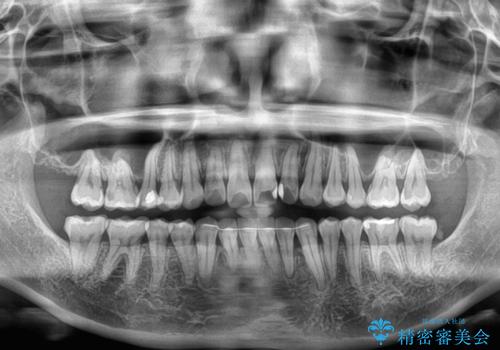

- 上下の前歯のでこぼこを気にして来院された患者様です。

職場の都合により、表側のワイヤー装置や着脱作業が頻繁なマウスピース矯正は困難とのことで、全く目立たない裏側矯正装置を用いて口元を整えることとしました。

途中転勤や出産があり、通院できない期間が長くありましたが、無事に歯列を整えることができました。